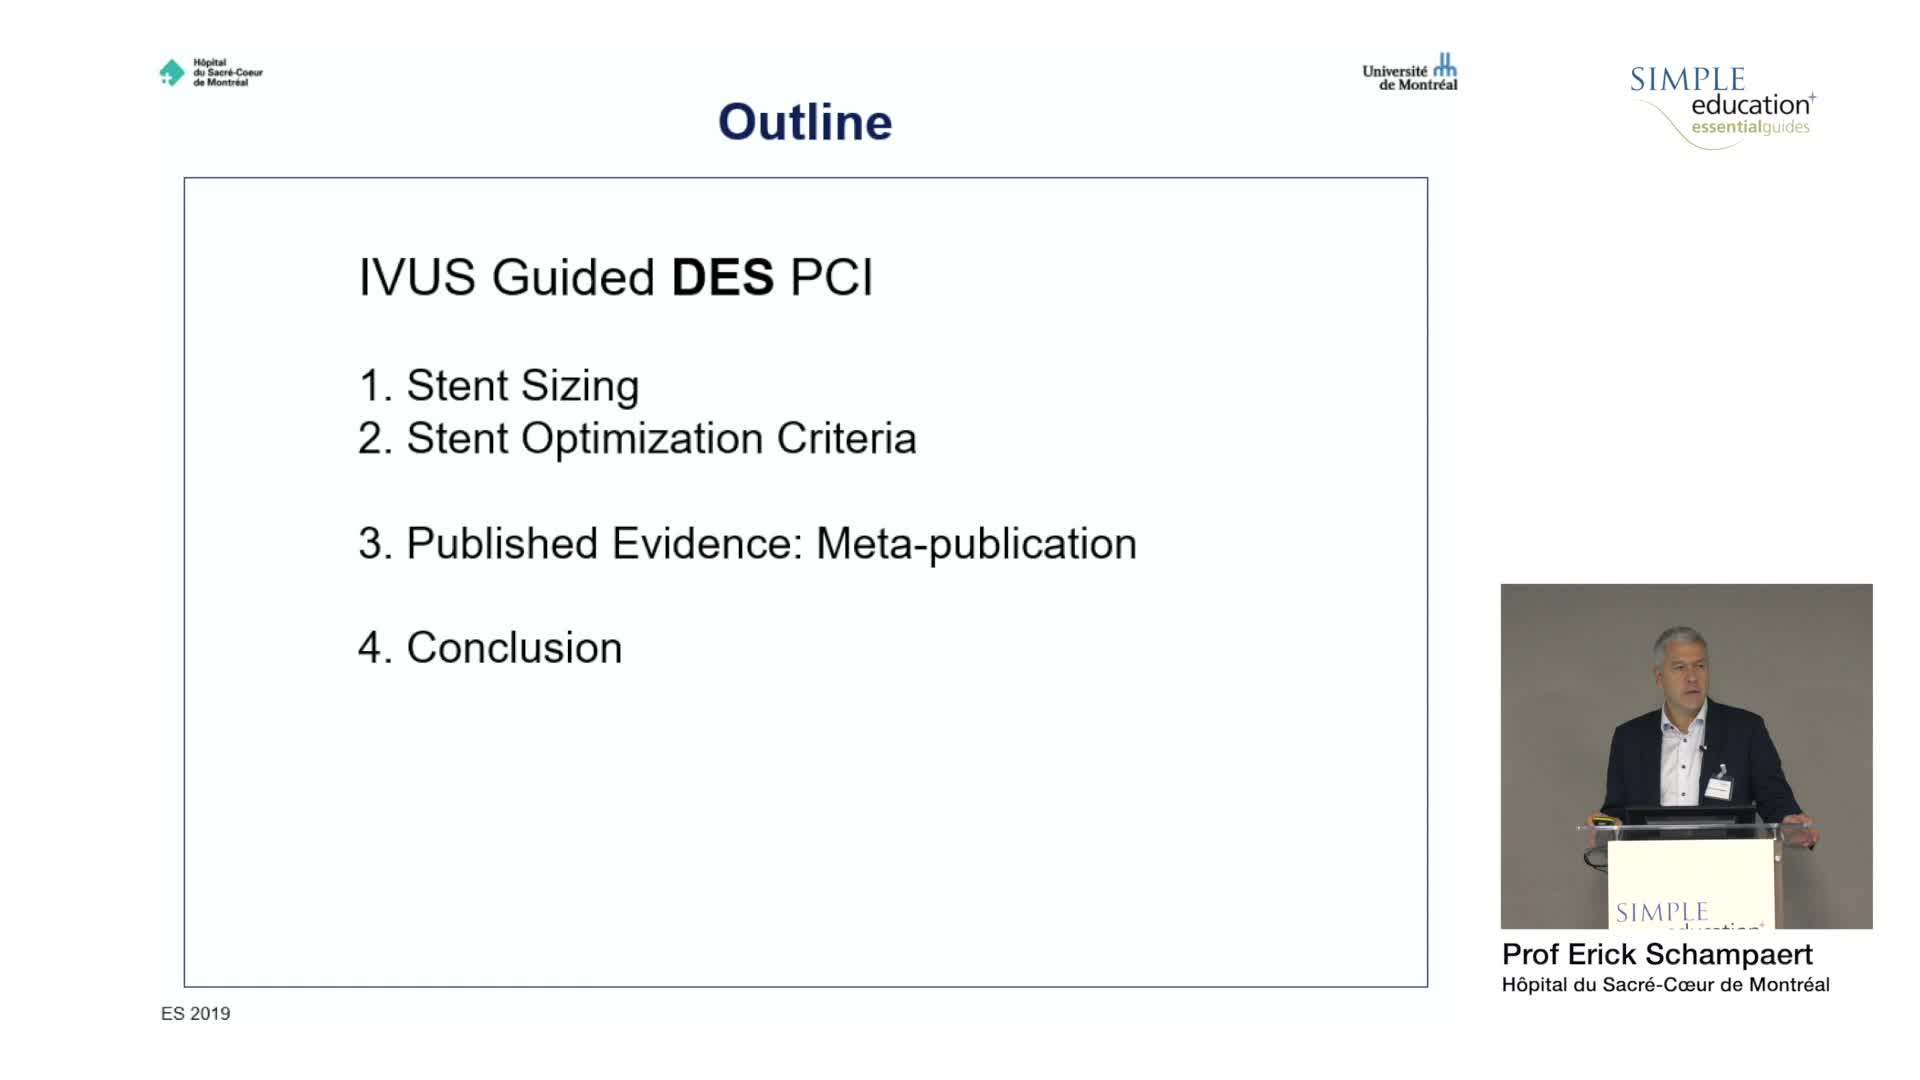

Evidence base for IVUS: to support use in routine practice - Prof Erick Schampaert